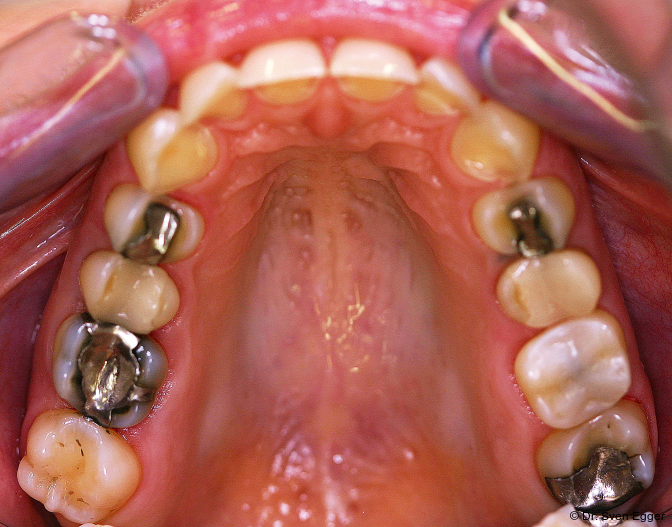

Bei der zahnmedizinischen Anamnese stellte sich ein hoher Konsum säurehaltiger Getränke (v. a. Coca-Cola light) heraus, welcher zu generalisierten Erosionen im Gebiss geführt hat. Die Zähne 36 und 47 wurden aufgrund endodontischer Vorbehandlung/Kronenfrakturen vor ca. vier Jahren entfernt. Der Leidensdruck, insbesondere verursacht durch die immer kürzer werdenden Frontzähne, bewog sie nach Aufklärung/Beratung zu einer Gesamtrestauration in allen vier Quadranten mit Presskeramikteilkronen und -veneers sowie drei Einzelzahnimplantaten.

Das OPG zeigt insuffiziente endodontische Versorgungen an 15, 25 und 46. Die Kieferhöhle rechts zeigt eine kirschgroße, kugelige Verschattung (Überweisung/Abklärung Kieferchirurgie).

- Dentalhygiene (Abformung für Situ-Modelle, Total-Wax-up, Fotostatus, Bissnahme in ZKP, Gesichtsbogenübertragung), Glasionomerzementfüllung 46